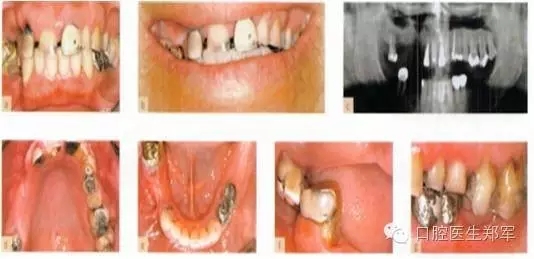

圖片5到12案例介紹了部分牙列缺損導(dǎo)致的功能缺失和美學(xué)受損。

形態(tài)缺陷的診斷包括:牙列缺損、后牙支撐減少、輕度到中度的垂直距離喪失,美學(xué)和功能障礙,以及不良修復(fù)體。

口腔疾病和功能障礙包括:繼發(fā)齲、可復(fù)性關(guān)節(jié)盤移位、繼發(fā)創(chuàng)傷、臨床附著喪失≥5mm超過(guò)30%的位點(diǎn)的嚴(yán)重慢性牙周炎。

圖5 a-g 局部缺牙、美學(xué)缺陷、牙列缺損、后牙牙合支撐喪失、部分牙段過(guò)度萌出、咬合垂直距離中度喪失(圖片由Dr. 0 Ghelfan提供) |